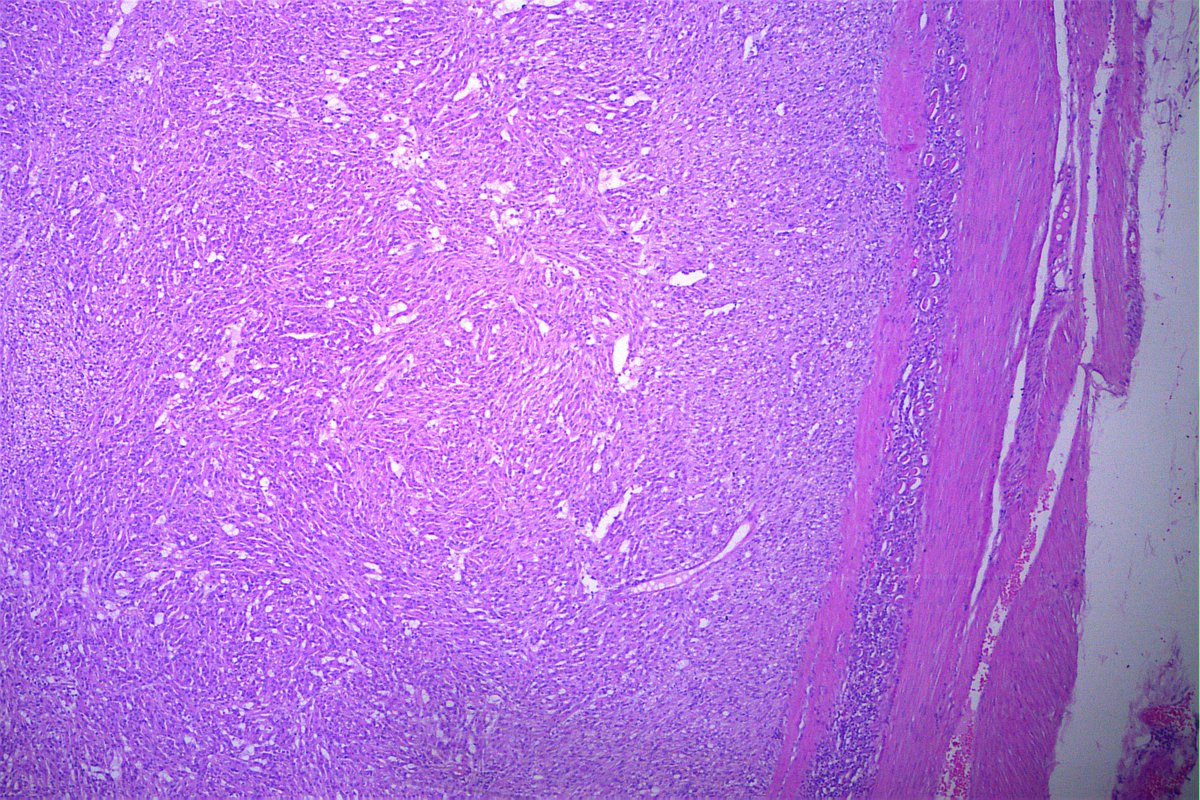

@GeronimoJrLapac

Ger么nimo Jr.

4 months

CASE OF THE DAY. M, 75 yo. Tumor in the sphenoid sinus. #geronimoscases #pathology #entpath